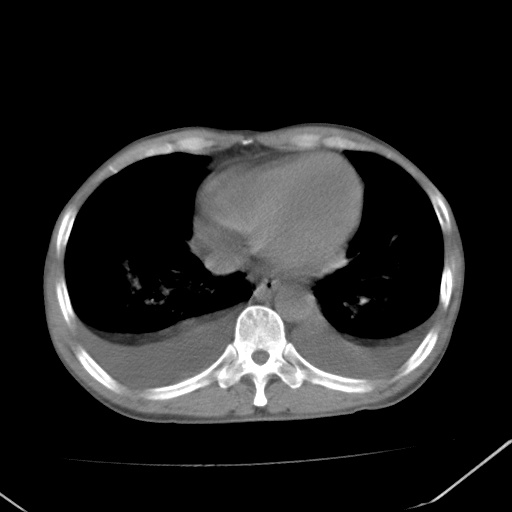

男、42岁、咯血3天。既往有甲亢、贫血、血尿蛋白尿史多年。血象:wbc:6.   中性粒:70.6%。

结合病史考虑双肺泡积血,双侧胸腔少量积液;肺水肿待排(肺水肿症状重)。

双肺堆成磨玻璃影,双测胸腔积液。考虑:肺水肿、间质性肺炎、真菌感染、ards、hiv感染、肺出血。

双肺野对称性磨玻璃影,分布于内中带,双侧胸水,患者有咯血。

左心房增大,考虑心衰,肺水肿。

双肺野广泛对称性磨玻璃影、实变影,以肺门为中心,主要分布于内中带,符合典型肺泡性肺水肿;伴双侧胸腔少量游离积液。结合患者既往病史且咯血就诊,支持多因素(尿毒症等)所致之肺水肿、肺出血、胸水;影像表现暂不考虑心源性水肿,且症状也不太符。需密切随诊结合临床治疗等进一步明确。

心影增大密度略低,双肺磨玻璃样高密度影及双侧胸腔积液,考虑心功能不全继发双肺肺水肿及双侧胸腔积液。心影密度略低,考虑贫血所致。